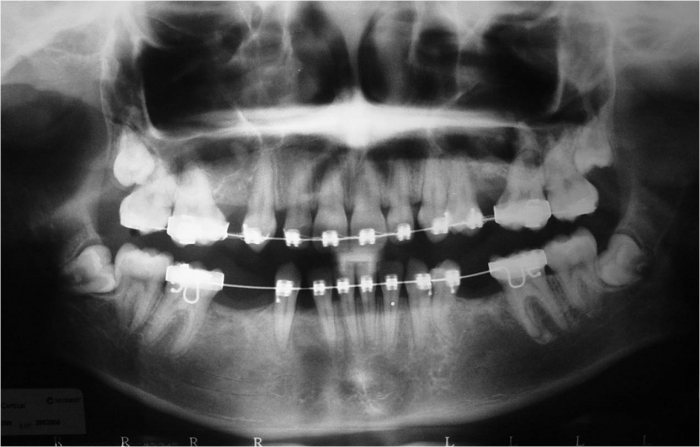

Raio após implantes instalados